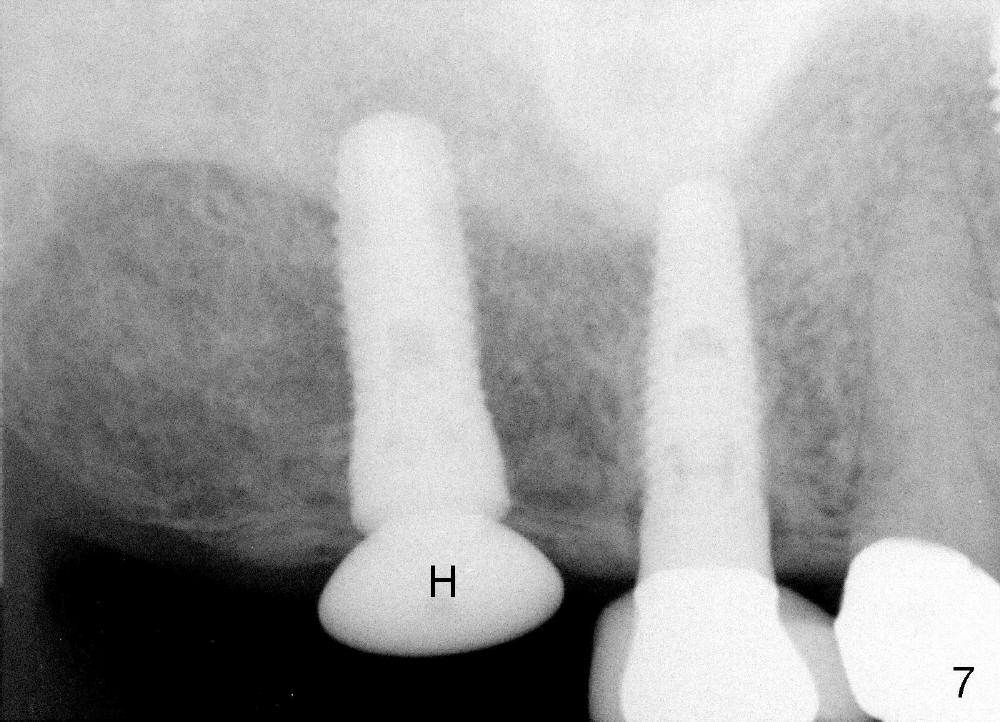

Analysis of preop PA suggests that the density of the cancellous bone is low at the site of the tooth #2. It is confirmed when a 2 mm pilot drill is used to initiate osteotomy. There is no drilling resistance once the pilot drill penetrates the cortex. A parallel pin is inserted for trajectory (Fig.1: P; 8 mm deep). The osteotomy is slightly moved distally with Lindermann bur and enlarged by inserting Bone Expanders from 2.6 to 3.8 mm at the depth of 12 mm (Fig.2). The osteotomy is then intended to move mesially and the depth is increased to 14 mm. Finally a 5.3x14 mm submerged implant is placed with insertion torque ~ 40 Ncm (Fig.3). The implant looks to have been tightly engaged into the bone (Fig.4). In one word, minimal bone removal is required for implant placement in the soft bone, particularly in the maxillary posterior region. A 8.2 mm healing abutment is placed; the flaps are closed by Chromic gut suture and perio glue (Fig.5). The wound heals normally 1 week postop (Fig.6). Fig.7 shows X-ray 3 months postop (H: healing abutment). Soft tissue looks healthy 4 months postop before (Fig.8) and after (Fig.9) removal of the healing abutment for restoration. There is no bone loss 7 months post cementation and 11 months postop (Fig.10 C: crown). It appears that bone expansion prevents bone resorption. There is no bone resorption 1 year 9 months post cementation. The implant is functioning 3 years 9 months post cementation (Fig.11).